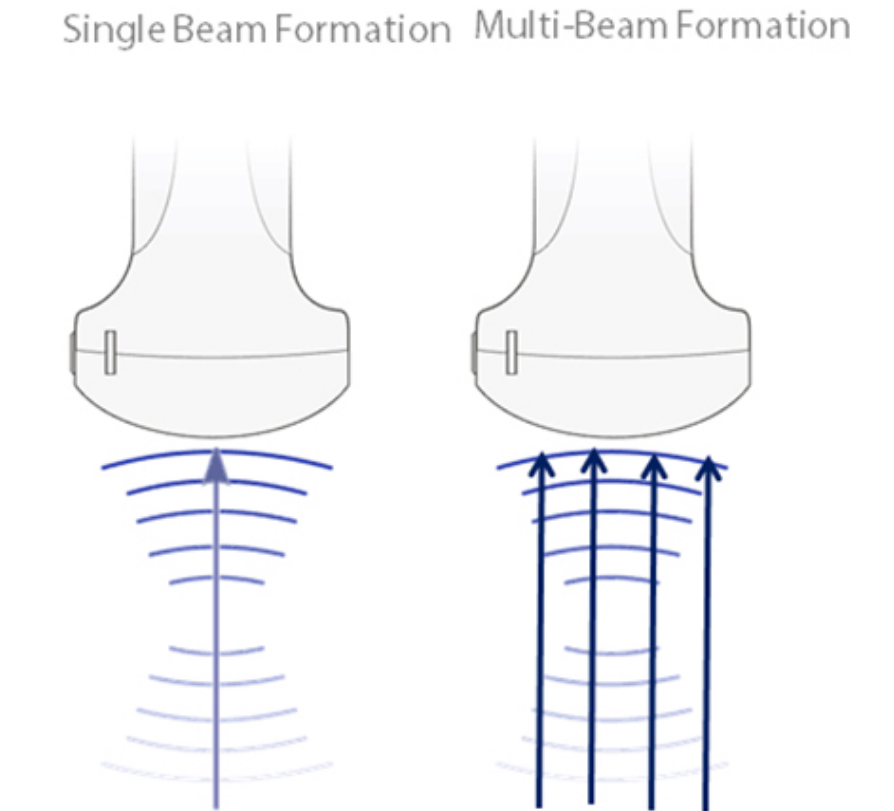

iBeam?

?? ?? ?? ??? ???? ?? ??? ??? ? ?? ?? ???? ???? ???? ???? ? ????.